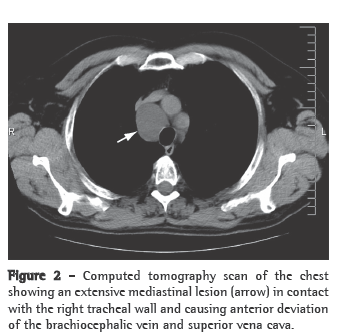

Computed tomography of the chest revealed a right paratracheal mediastinal tumor, 4.5 cm in diameter, in contact with the right tracheal wall and causing anterior deviation of the brachiocephalic vein and superior vena cava. The mass had regular borders and spontaneous low density, was homogeneous, and showed no enhancement after administration of contrast medium (Figure 2).

The presumed diagnosis is made based on the detection of a cystic lesion on a chest X-ray or a computed tomography scan of the chest.(5) On X-rays, lymphangiomas of the mediastinum appear as well-circumscribed, round masses of homogeneous density,(5) and computed tomography of the chest demonstrates the involvement or deviation of natural structures, absence of calcification, and various high attenuation areas within the lesion.(2)